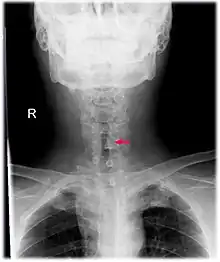

Neck AP x-ray of patient with post-intubation subglottic stenosis, as shown by the narrowing in the tracheal lumen marked by the arrow.

CT scans and MRI (magnetic resonance imaging) can help in diagnosis. X-rays can determine the location and size of the narrowed airway portion. Optical coherence tomography (OCT) can help observe the progression of the injury. Esophageal pH monitoring can help detect any acid reflux, which can worsen the condition. An endoscope can be inserted and used to see the vocal cords, airway, and esophagus. Spirometry is a useful way to measure respiratory function. People affected by subglottic stenosis have a FEV1 of over 10.[2]